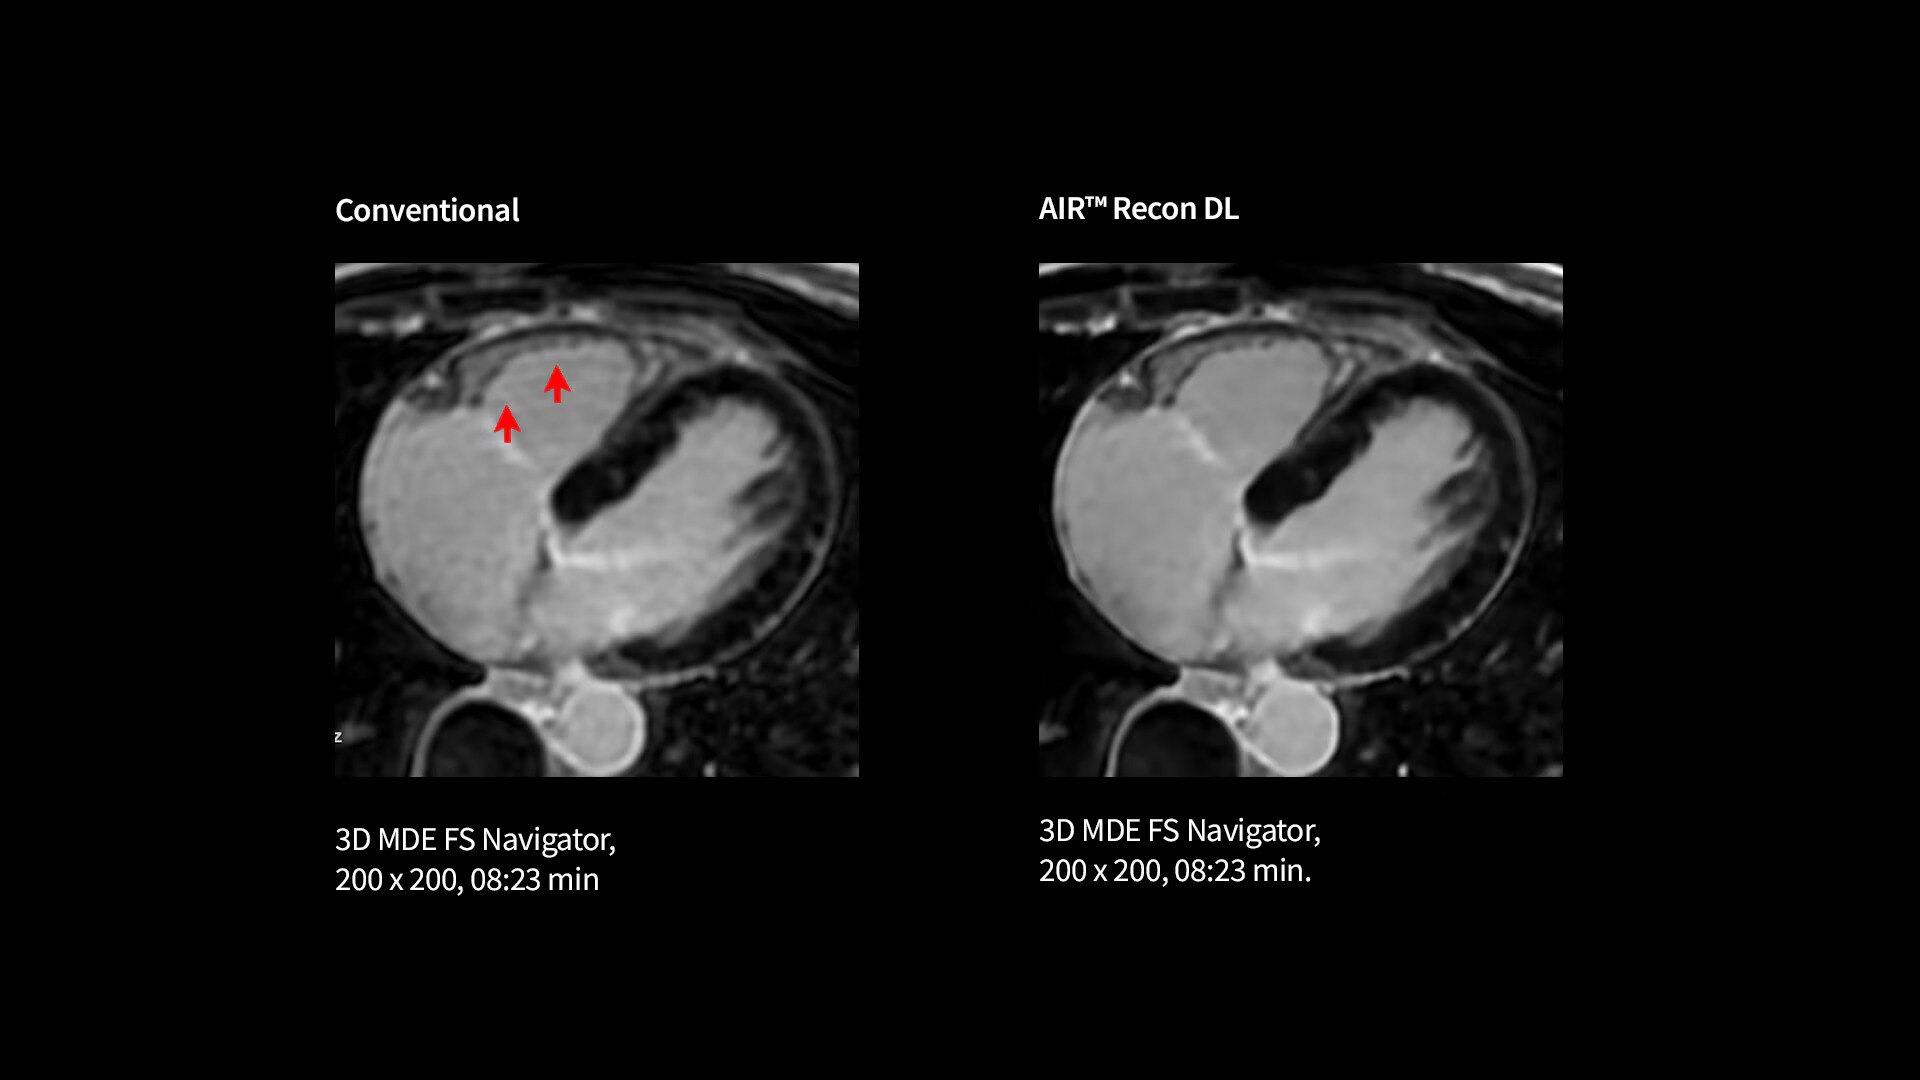

Improve SNR and image sharpness by up to 60% with AIR™ Recon DL

Every step of our cardiac MR assessment is compatible with our pioneering deep-learning algorithms, including: morphology, function, perfusion, mapping and myocardial viability with

late enhancement.

Your teams can capture clarity with AIR™ Recon DL, a revolutionary technique to boost image quality, providing accurate anatomic information and advanced soft tissue contrast. It’s already transformed the lives of millions of patients worldwide since 2021. Thanks to Sonic DL™ they can also now assess cardiac viability faster than ever before, with as little as 15 to 20 minutes per scan.*†